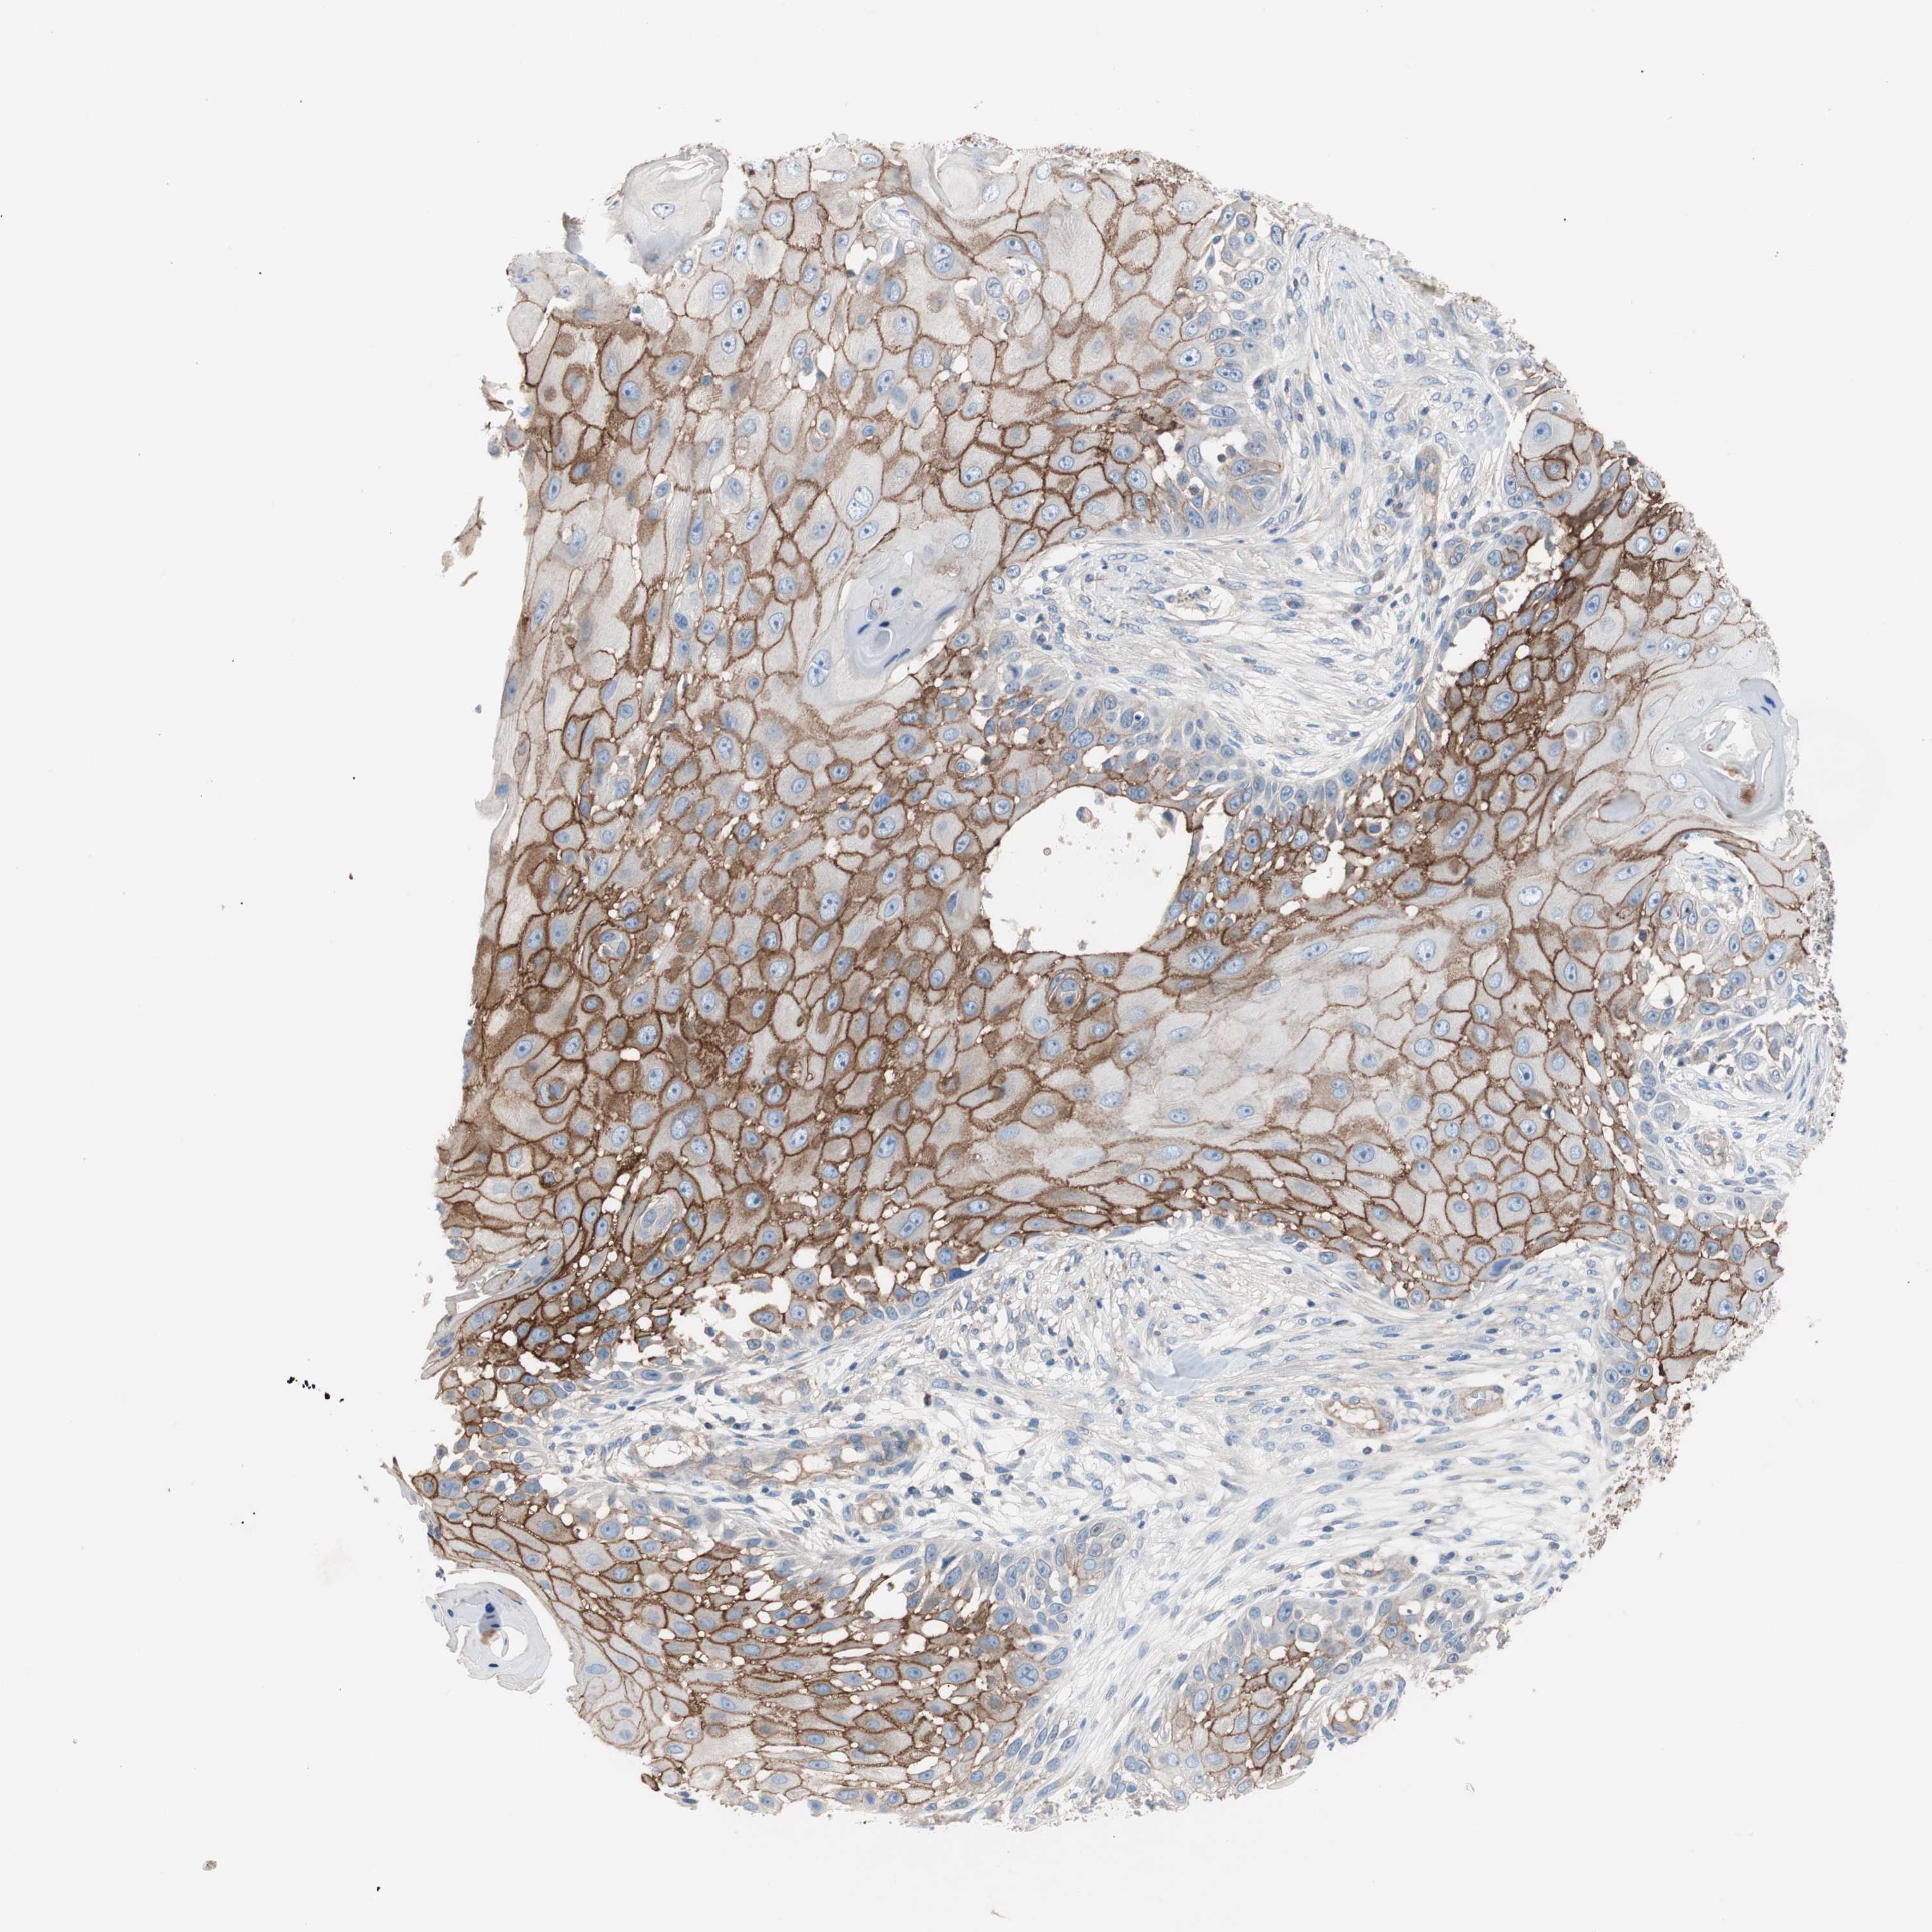

Antibody HPA006970

Staining

High

Intensity

Strong

Quantity

>75%

Location

Cytoplasmic/membranous

Squamous cell carcinoma, NOS